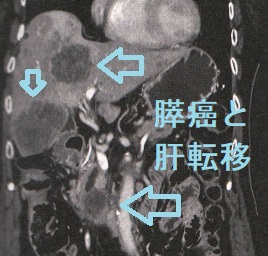

膵臓がんが転移しやすいのは、近くにある胃・十二指腸です。遠隔転移としては肝臓がもっとも多く、[後は甲状腺分化癌(乳頭癌,濾胞癌)と同じく]肺、脳、骨です。 遠隔転移膵臓癌の治療目標は、延命と症状の緩和です。遠隔転移膵臓癌の化学療法の第一選択肢としてゲムシタビン(ジェムザール®)が推奨されます。